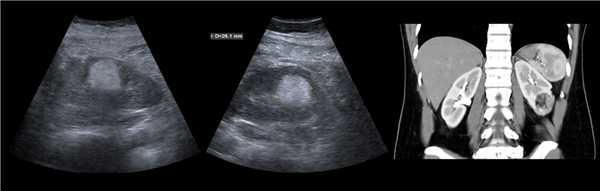

Рисунок. У новорожденного на УЗИ почек определяется гидронефроз (1) и расширенный мочеточник (2) справа. В мочевом пузыре двустороннее уретероцеле (3). При исследовании левой почки структурных изменений не выявлено.

Рисунок. На УЗИ определяется удвоенная чашечно-лоханочная система, расширена лоханка верхнего сегмента (1) и мочеточник на всем протяжение (2, 3), в мочевом пузыре уретроцеле (4). Полное или неполное удвоение чашечно-лоханочной системы возможно увидеть с помощью КТ-урографии.